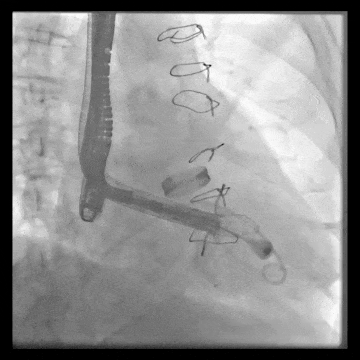

術(shù)中DSA顯示起搏器導線的干擾,右心室造影確定瓣環(huán)位置,操作空間小

術(shù)后DSA